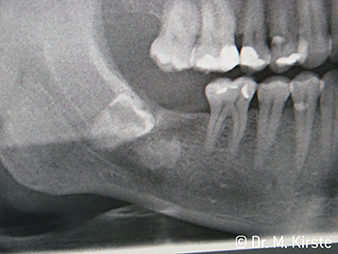

Денталните наконечници WS-91 и WS-91 L G за първи път комбинират предимствата на хирургичен прав и обратен наконечник. advantages (Фиг. 1). Разширеният ъгъл между опашката и оста н борера позволява добър достъп до редицата от зъби букално и оклузално едновременно. (Фиг. 4). Разместените зъби удобно могат да бъдат разделени (Фиг. 6 и 7). Лекарят по дентална медицина разполага със значително по-добра видимост в обработваната зона, отколкото с предходните инструменти. Д-р Марио Кирсте от Франкфурт/ Одер споделя, “Ако леко завъртя обратния наконечник, мога да работя сравнително бързо и безопасно в ретромоларната зона. Инструментът има потенциал да застане в различни позиции, зададени от потребителите на прави и обратни наконечници.” (Фиг. 2-5)